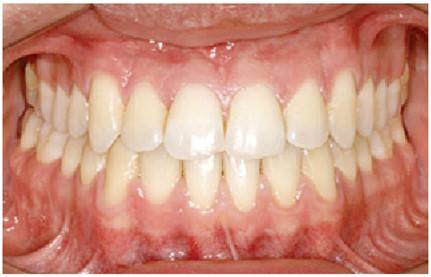

구글에서 asymmetry(비대칭), orthodontics(치아 교정)로 검색하면 가장 상위에 뜨는 논문 사진을 보겠습니다. 교정으로 치아의 비대칭이 크게 좋아진 모습을 볼 수 있습니다.

위 사진만 보면, 치아 교정으로 안면 비대칭도 좋아질 것 같습니다. 그러나, 입을 다문 사진을 보면 얼굴의 비대칭은 교정되지 않았습니다.